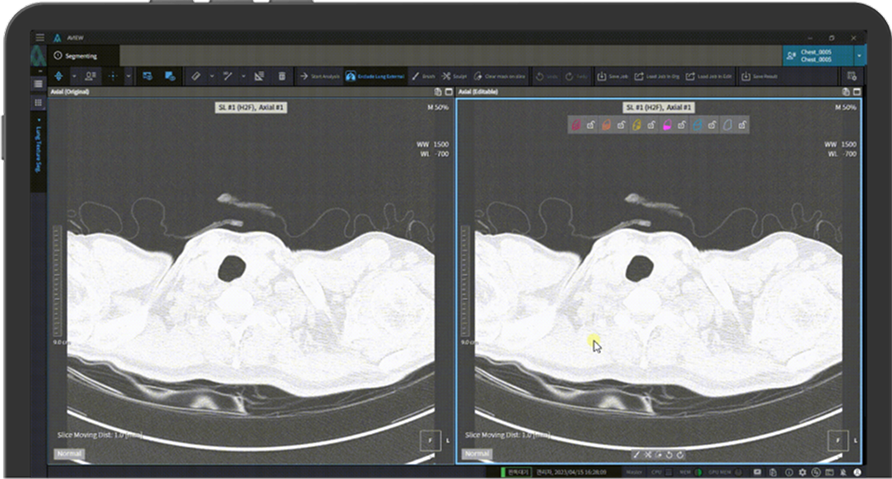

Multi-Layout

Comparison and Modification of Patterns

The analyzed pattern can be compared with the original pattern in real time and can be easily adapted.